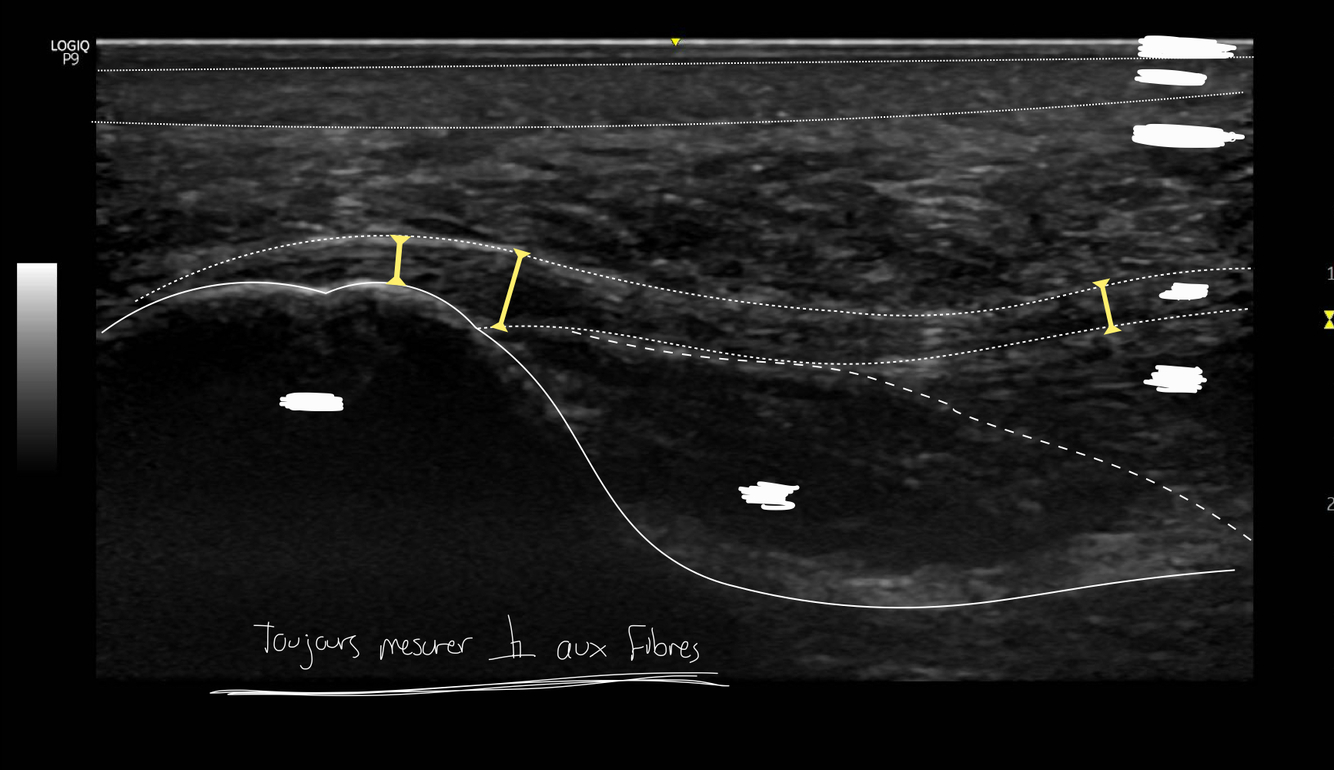

Q

Identifie la région du pied analysée ici

A

Il s’agit de la tubérosité médial du calcanéus avec le fascia et les épaisseurs de la peau au dessus